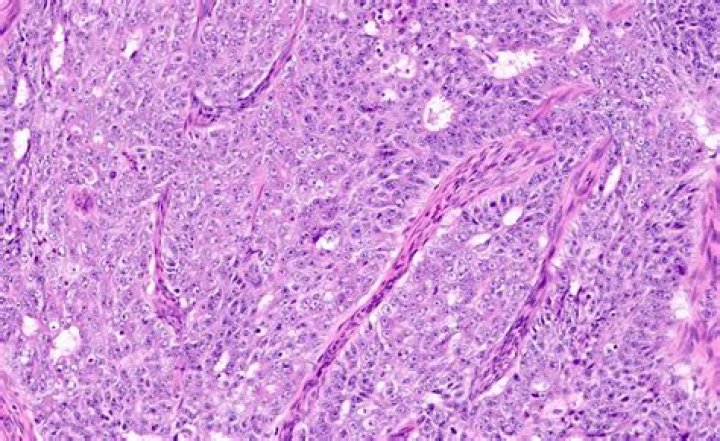

Endometrioid carcinoma of the endometrium is the most common type of endometrial carcinoma. The microscopic appearance of the tumor resembles that of the proliferative endometrium, with a variable degree of glandular complexity and cellular pleomorphism.